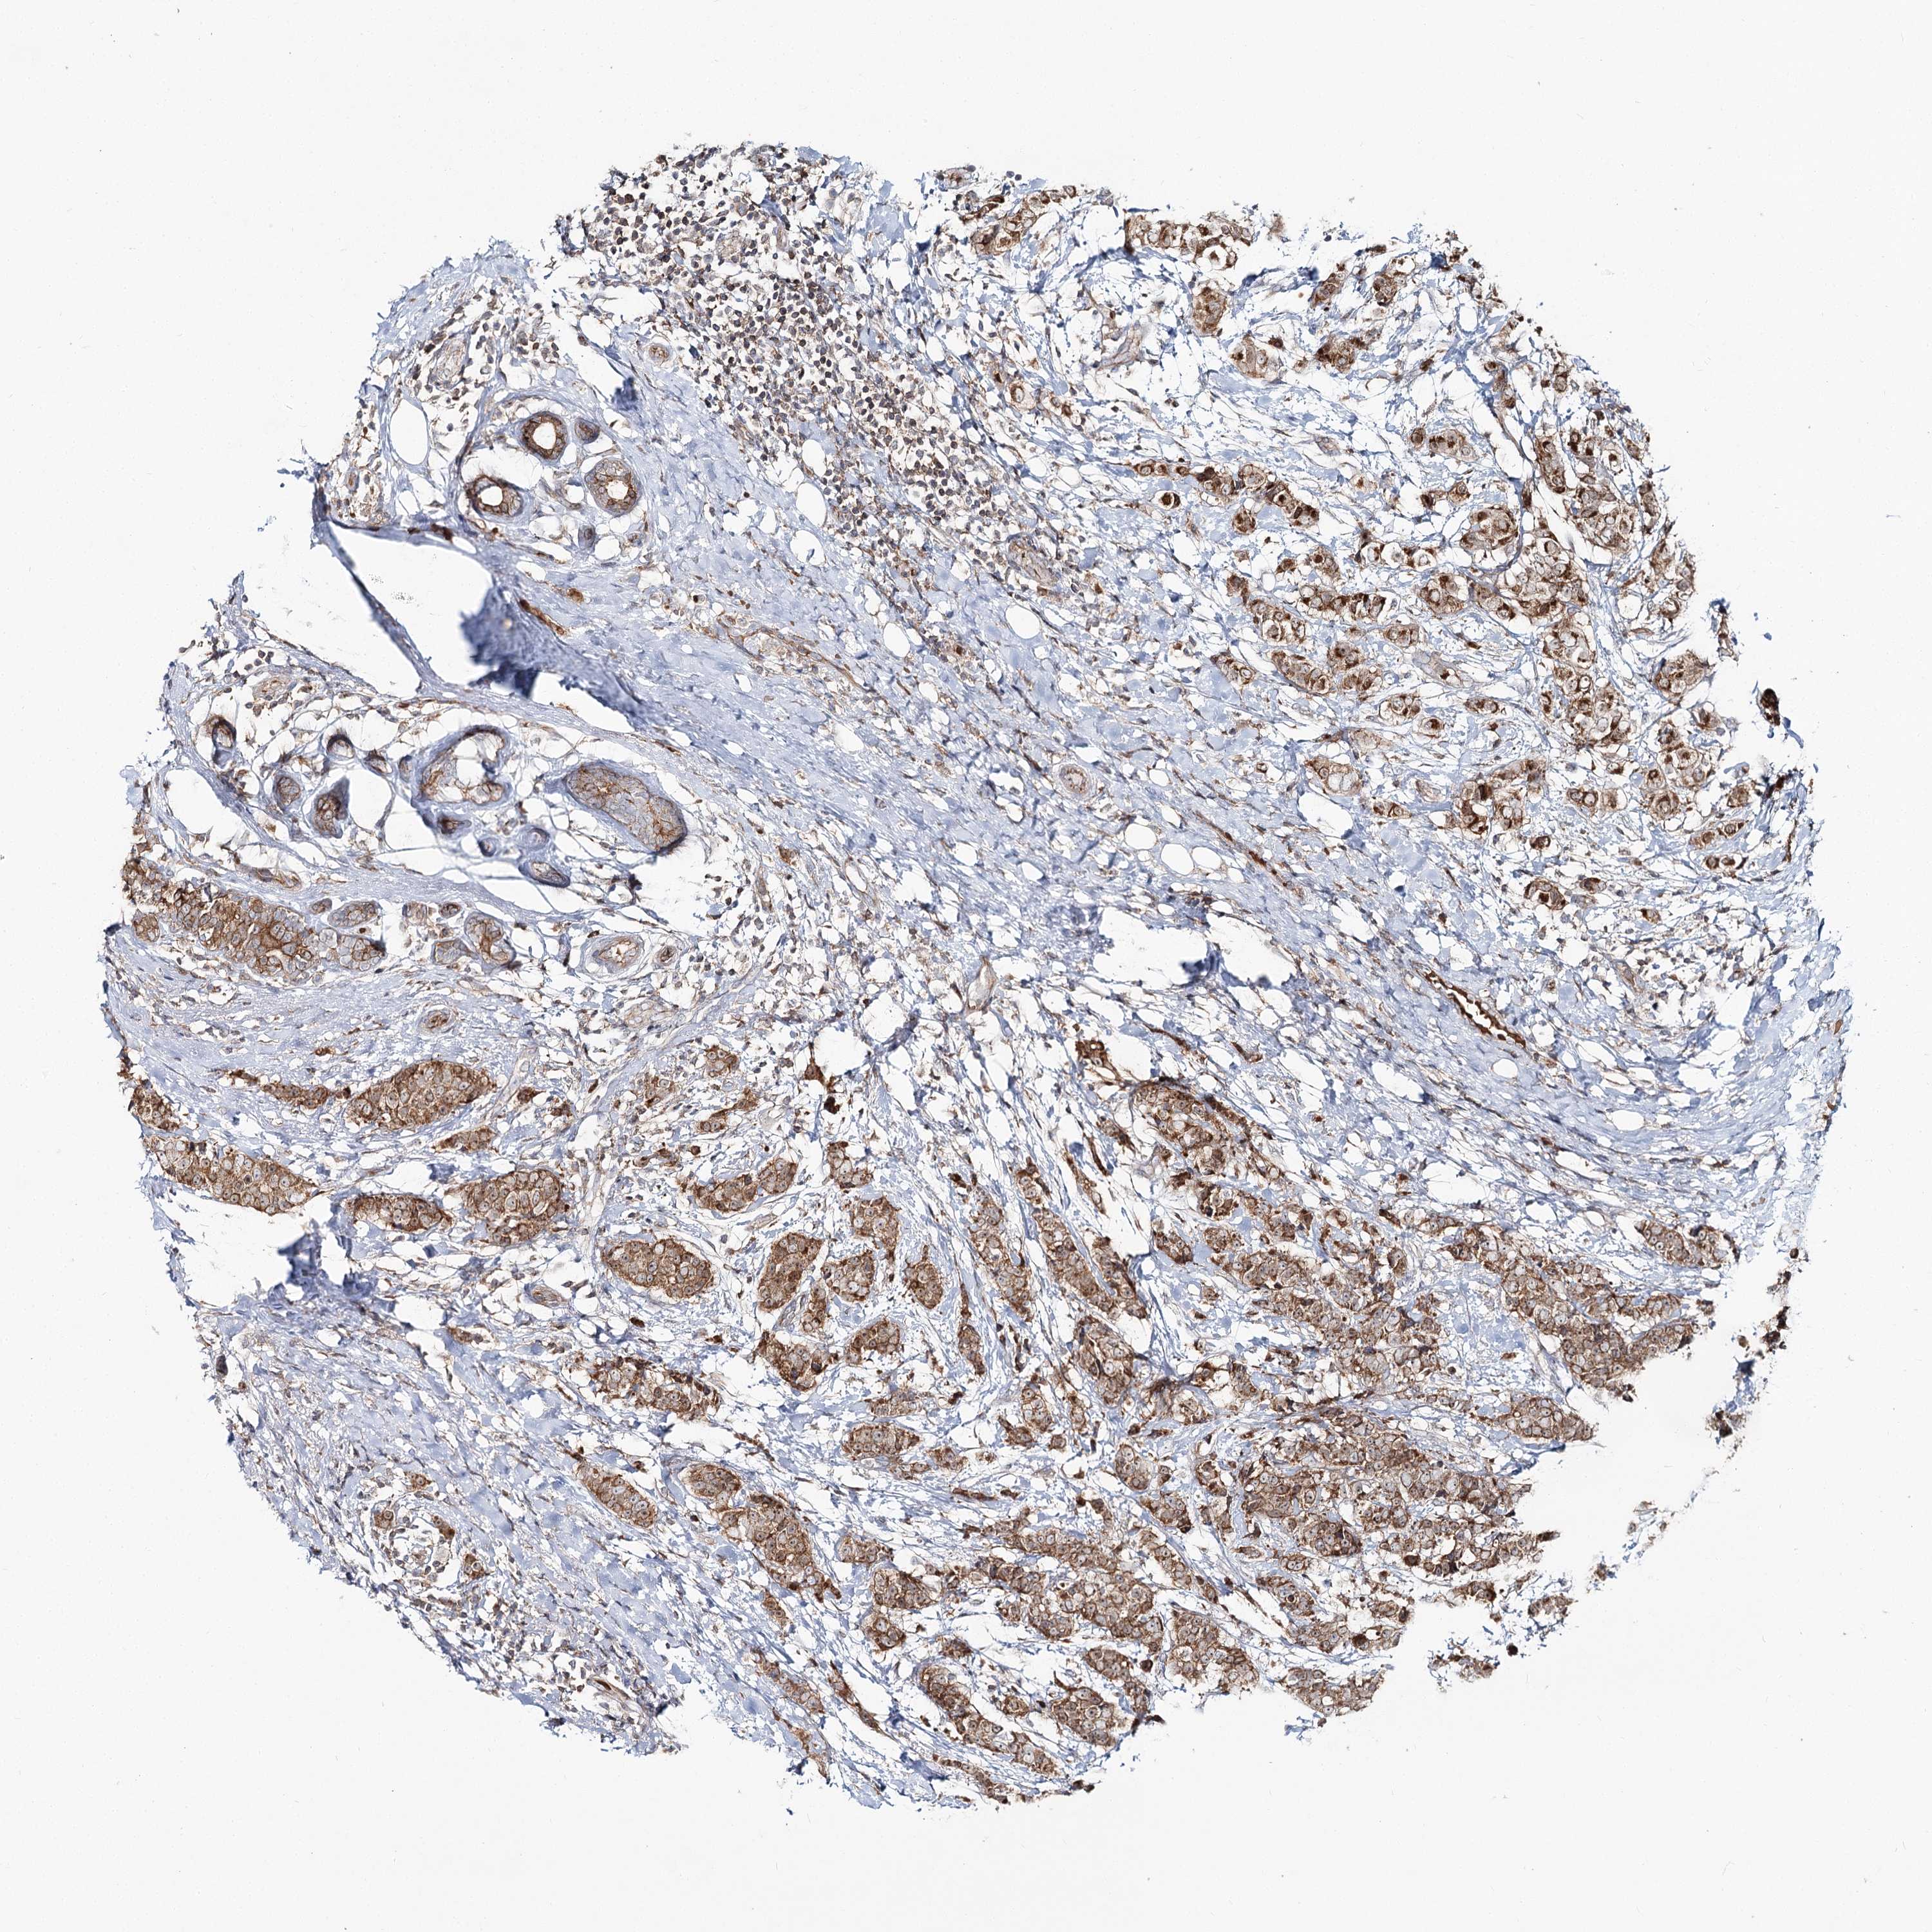

CANCER BREAST CANCER Show tissue menu

BRCA TCGA BRCA VALIDATION PROTEIN EXPRESSION